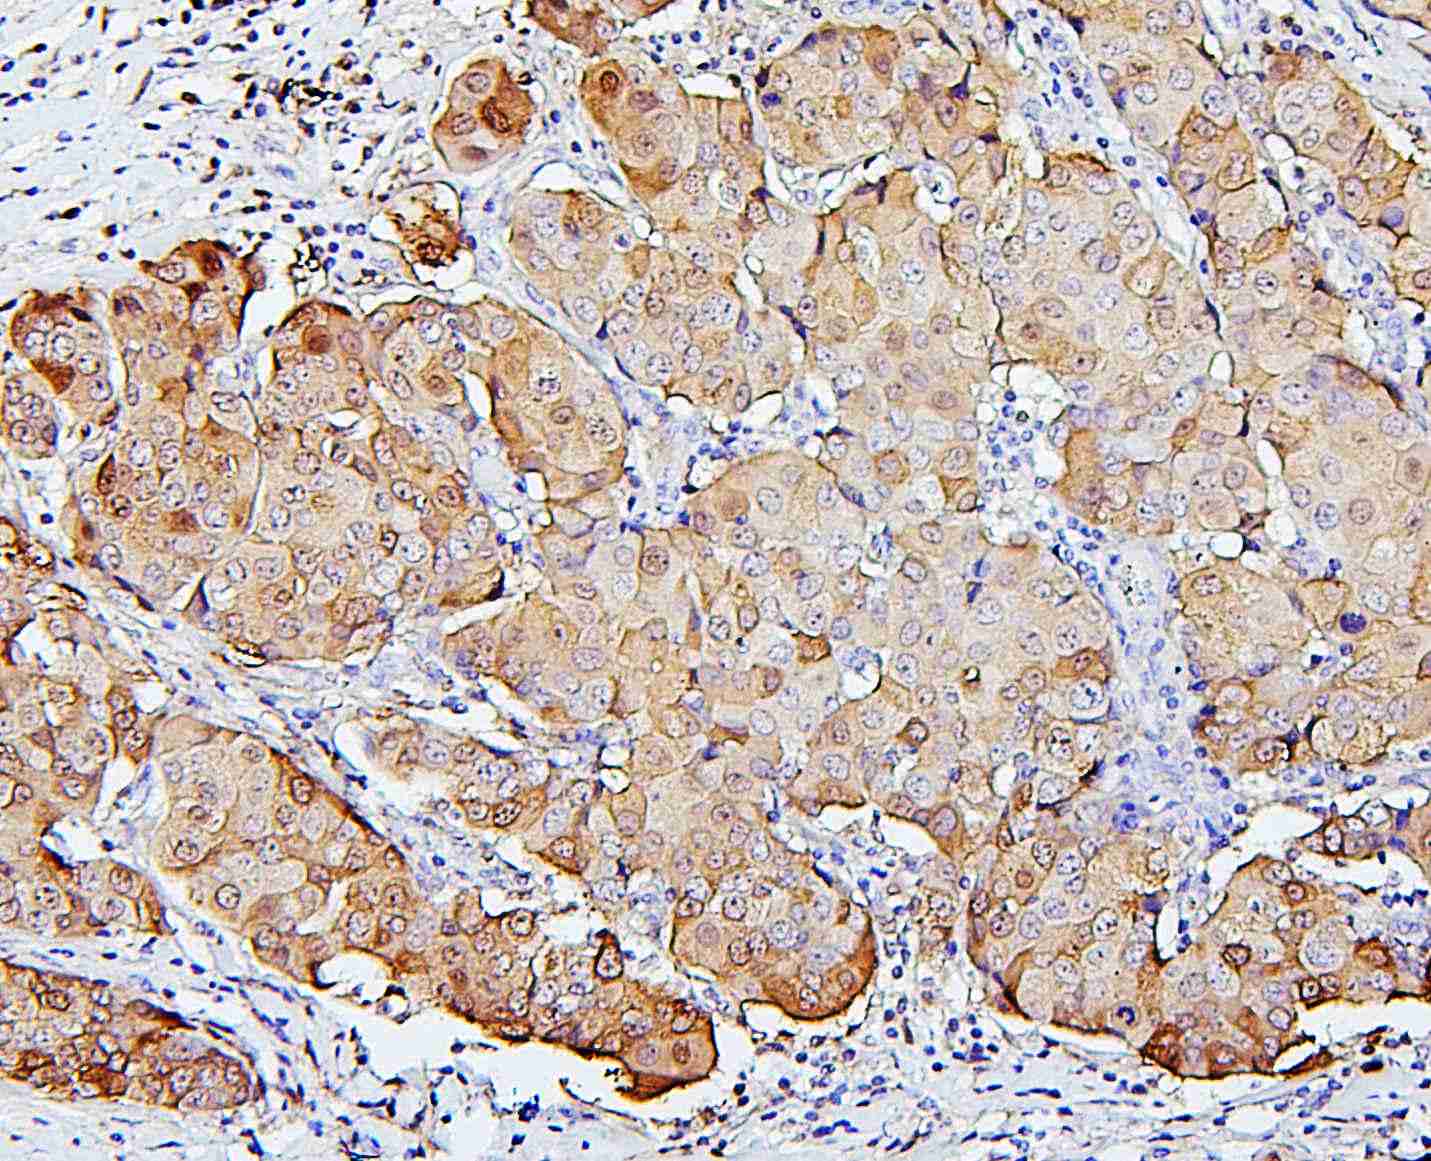

IHC analysis of P62/SQSTM1 using anti-P62/SQSTM1 antibody (M00300-1).

P62/SQSTM1 was detected in a paraffin-embedded section of human lung cancer tissue. Biotinylated goat anti-mouse IgG was used as secondary antibody. The tissue section was incubated with mouse anti-P62/SQSTM1 Antibody (M00300-1) at a dilution of 1:200 and developed using Strepavidin-Biotin-Complex (SABC) (Catalog # SA1021) with DAB (Catalog # AR1027) as the chromogen.